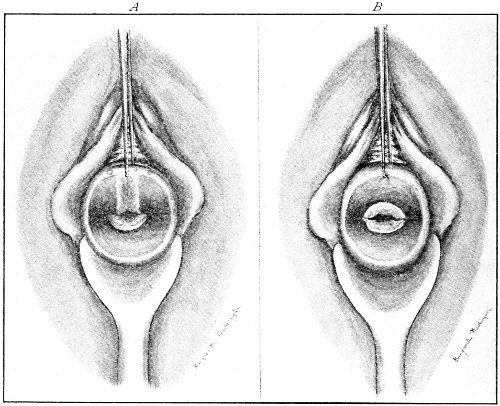

An accurate knowledge of the anatomy and mechanism of the female perineum is essential to an understanding of the nature and treatment of injuries to this structure. The anatomical structures lying between the anus behind and the symphysis pubis in front are those that most directly interest the gynecologist. Proceeding from 57 below upward, we find the following structures lying in superimposed planes: the skin, the superficial fascia, the deep layer of the superficial fascia, the transversus perinæi and the sphincter vaginæ muscles, the anterior layer of the triangular ligament, the posterior layer of the triangular ligament, the levator ani muscle (Fig. 19).

Fig. 18, A.—Superficial structures of the female perineum (Weisse).

Fig. 19.—Dissection of female perineum: on the left side the perineal muscles are exposed by the reflection of the perineal fascia; on the right side the muscles and the superficial layer of the triangular ligament have been removed, thereby exposing the deep layer of the ligament. S. V., Sphincter vaginæ muscle.

The vagina passes through these structures. They surround and support the ostium vaginæ as the fascia and muscles surround and support the opening of the rectum or the anus. The muscles and fasciæ are attached in the median line between the anus and the vagina, and therefore this part of the body, which is called the perineum, is supported or maintained in its 58 proper position by these various structures. The transversus perinæi arises from the ramus of the ischium and is inserted in the perineum. The bulbo-cavernosus, or sphincter vaginæ, arises in the perineum and is inserted in and about the clitoris. The inner fibers of the levator ani arise from the symphysis pubis and are inserted in the perineum and the lower part of the vagina (Fig. 20). When these muscles contract, their action, therefore, is to draw the perineum upward and forward. At the same time the anus is drawn upward and forward, and so also is the posterior margin of the ostium vaginæ and the lower portion of the posterior vaginal wall.

Fig. 20.—Dissection of female perineum, showing the deeper structures after removal of the levator and sphincter ani muscles.

The vagina has no circular sphincter like the anus, but 59 the vaginal month is kept closed by the action of the transversus perinæi, sphincter vaginæ, and levator ani muscles, which draw the perineum forward, and thus keep the posterior vaginal wall in apposition with the anterior wall.

Fig. 21.—Muscular floor of the pelvis seen from above.

This sling of muscles and fascia, which surrounds and supports the opening of the vagina, may readily be felt in the nulliparous woman by introducing the finger in the vagina and pressing backward and outward toward the ischio-rectal fossa. We then feel plainly, immediately within the ostium vaginæ, a firm resisting band of tissue, apparently about half an inch broad, embracing the posterior portion of the lower vagina. This band is formed by the inner edges of the various muscles and planes of fascia that have been described.

Fig. 22.—Sagittal section showing relations of the several layers of fascia within the pelvic floor (Dickinson).

The vagina extends, as a transverse slit in the pelvic floor, upward and backward, approximately in the direction 60 of a line drawn from the ostium vaginæ to the fifth sacral vertebra. It is approximately parallel with the conjugate of the brim, so that when the woman is erect the long axis of the vagina is inclined at an angle of 60° to the horizon. The vagina is not a vertical open tube: it is a slit in the pelvic floor, in health always closed by the accurate apposition of the anterior and posterior walls (Fig. 21). The anterior vaginal wall is about 2½ inches long in a vertical mesial line. The posterior vaginal wall is about 3½ inches long. The vaginal walls are triangular in shape, being broader above than below. The shape of the normal vagina at the pelvic outlet is shown by Fig. 23. The section here shows the vaginal 61 slit of the shape of the letter H. The portions of the slit extending backward and somewhat outward are called the vaginal sulci or furrows. They are directions of diminished resistance in which tears are liable to occur.

Fig. 23.—Section illustrating the characteristic form of the vaginal cleft (Henle): Ua, urethra; Va, vagina; L, levator ani; R, rectum.] 62